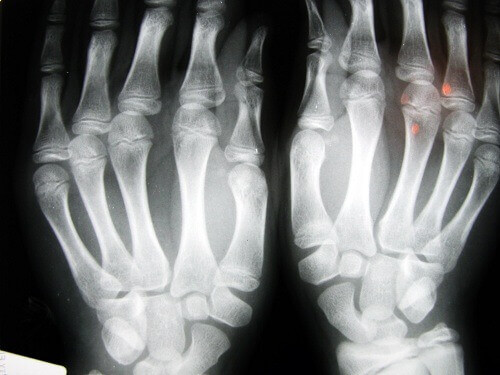

De som lider mest av detta problem är vuxna över 40 år. De områden där knäckning av lederna resulterar i störst nedbrytning är händerna (fingrarna och handlederna) samt nacken. Det bästa sättet att undvika detta problem är att motionera på ett sätt som passar din ålder och fysiska tillstånd. Promenader och simning är de mest rekommenderade formerna av motion.